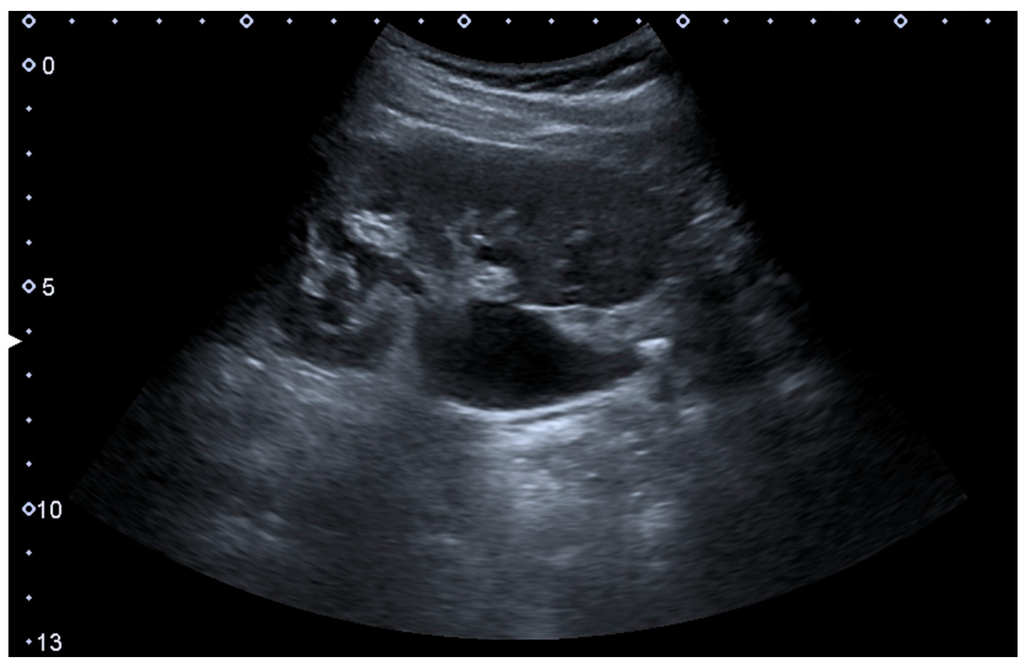

The hydronephrosis is typically graded visually and can be divided into five categories going from a slight expansion of the renal pelvis to end-stage hydronephrosis with cortical thinning (Figure 15) [16]. The evaluation of hydronephrosis can also include measures of calyces at the level of the neck in the longitudinal scan plane, of the dilated renal pelvis in the transverse scan plane and the cortical thickness, as explained previously (Figure 16 and Figure 17) [4].

Figure 15. End-stage hydronephrosis with cortical thinning. Measurement of pelvic dilatation on the US image is illustrated by ‘+’ and a dashed line.